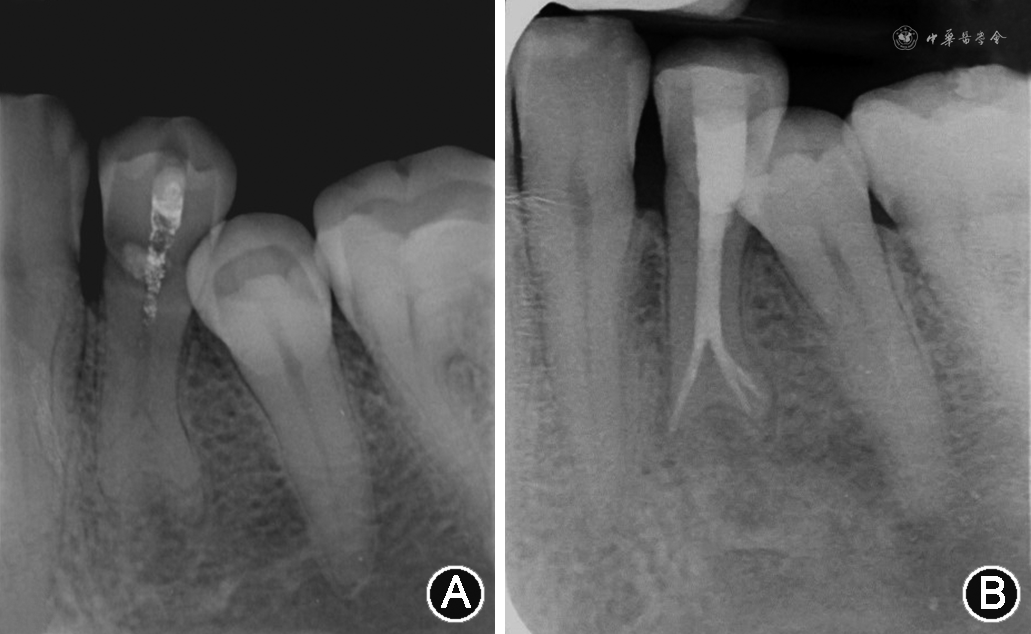

3.牛牙症和C形根管:牛牙症是一种髓腔内部形态变异,最早于1913年由Keith教授在描述史前人类尼安德特人牙齿化石时提出。牛牙症的牙齿在釉质牙骨质界处缺乏收缩,其特征是髓室垂直向延长、髓室底顶端向根方移位以及牙根分叉[29]。这种倾向与偶蹄目动物,特别是公牛的牙齿情况类似,因而命名为牛牙症[30]。Madeira等[31]研究认为,牛牙症的诊断应包括以下几点:①牙颈部无明显缩窄;②宽的棱柱形牙根,从牙颈部到根尖部牙根的直径大致相同;③根尖部膨大、分叉、顶端略凹;④髓腔宽大并于根尖处分叉。基于上述标准,Madeira等[31]认为下颌第一前磨牙这种根管宽大分叉的特点并不足以作为诊断牛牙症的指征,更倾向于这是下颌第一前磨牙根管变异的一种常态,其研究报道下颌第一前磨牙牛牙症的发生率为0.42%。值得注意的是,一些双根的下颌第一前磨牙,其粗大的管腔通常在釉质牙骨质界下6~7 mm甚至更低的位置分叉[32]。本课题组收治的1例左下颌第一前磨牙根管治疗患者,呈现典型的如Madeira等[31]描述的特征(图2),其牙冠牙颈部无明显缩窄,根管上段管腔粗大,于根尖1/3分成3个独立根管,属于典型的牛牙症患牙。此外,Aricioğlu等[33]研究显示,牛牙症与C形根管的发生高度相关,国内亦有相关病例报道[7],临床医师在治疗牛牙症患牙时需警惕患牙可能同时存在C形根管系统(图3)。

患者男性,36岁。主诉:左下后牙隐痛1周。现病史:1周前左下后牙出现自发性阵发性隐痛,持续几分钟后缓解,有冷热刺激痛,无明显夜间痛及咬合痛。既往史:否认系统性疾病史。口腔检查:34远中邻面牙色充填体,边缘不密合呈浸墨状改变,无探痛,冷测试敏感,热测试反应迟钝,叩诊(+),无松动,近中龈乳头稍红肿。根尖片示:34充填体下方密度减低区近髓,根管中上2/3可见粗大单根管影像,根尖1/3根管影像模糊,根尖部未见透射影。